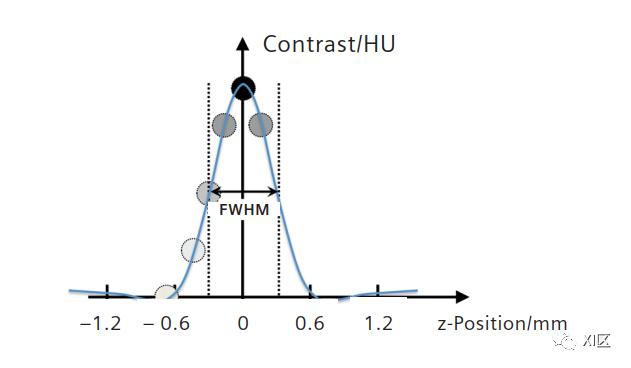

所有这些数据现在都可以用来重建定义良好的薄层图像,其薄层图像层厚接近于准直的薄层宽度。层厚灵敏度曲线(SSP)为钟形曲线。它是X射线管投射到探测器上的焦点的梯形几何体和螺旋扫描期间的直线扫描床运动卷积的结果。因此,X射线管焦点的大小也起着决定性的作用。要创建窄的SSP和高分辨率数据,需要一个小而稳定的X射线焦点。

在西门子SOMATOM Perspective上获得的钟形层厚灵敏度剖面。半高宽(FWHM)为标称层厚。一个小的结构,例如一个0.3毫米的小球,只在切片的中间用完全的对比度来描绘。切片中心以外对比度下降。(0.6 mm准直,H70s重建核)

上图显示了SOMATOM Perspective的实际SSP,最小标称切片宽度为0.6 mm。SSP可以理解为小对象沿z轴在数据体中移动时对比度的变化。只有在切片的中心,小物体,例如一个0.3 mm的球体被描绘成全对比度。离开切片中心时,对比度降低。对比度降低到50%的SSP宽度称为半高宽(FWHM),通常用于定义有效切片厚度。